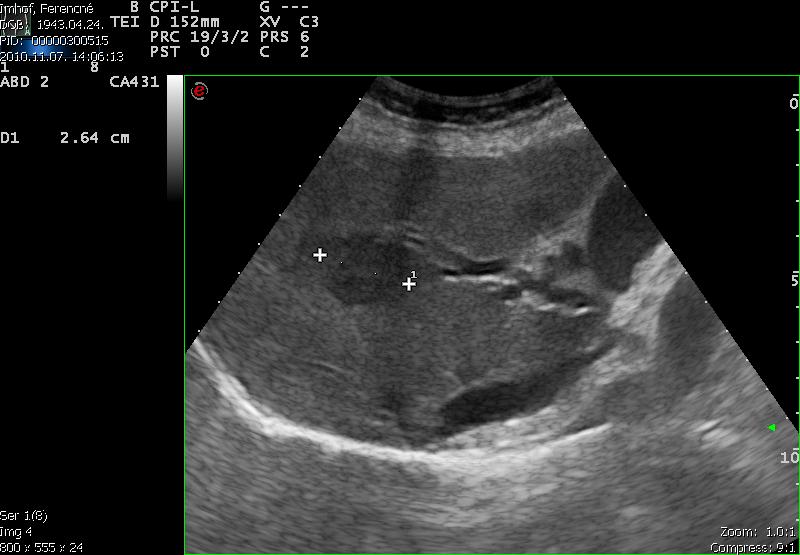

Idős hölgy sárgasággal